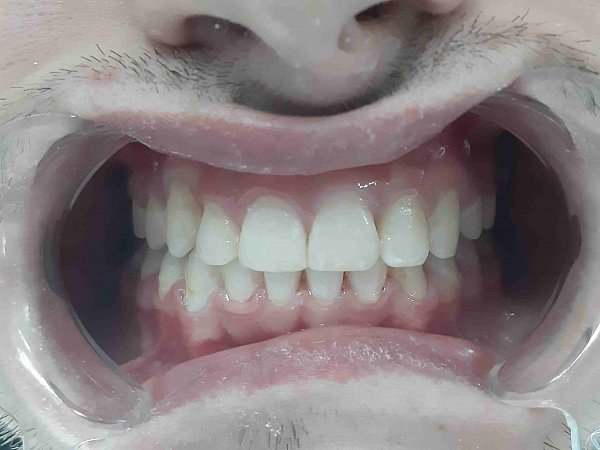

Пациентка 16 лет. Жалобы на неправильное положение зубов, нарушение прикуса.

Ортодонтического лечение проводилось на

Диагноз: Мезиальная окклюзия, тенденция к вертикальной резцовой дизокклюзии, скучное положение зубов.

Фактический срок лечения 25 месяцев

Пациентка обратилась по эстетическим показаниям, изначально у нее выявлено: недостаточная ширина улыбки, снижение высоты нижней трети лица, отсутствие плотного смыкания зубов в боковом отделе, сужение зубных рядов. Так же пациентка была очень недовольна формой и цветом передней группы зубов. Был поставлен диагноз — Мезиальная окклюзия. Сужение зубных рядов. Нарушение эстетики.

Основные пожелания пациентки — иметь ровный зубной ряд с правильным смыканием и положением зубов, но

Что было сделано:

-

Выровняли дугу улыбки с помощью

брекет-системы и техники многопетлевых дуг. - Провели коррекцию соотношения челюстей, добились нормализации формы и размеров зубных рядов.

- В области передней группы зубов были оставлены промежутки, для возможности увеличения размеров зубов

- Ортопедом фиксированы цельнокерамические виниры. Цвет и форма подбирались совместно с пациентом.

В итоге зубы стали не просто ровными, а идеальными: по форме и размерам. И цвет- главное пожелание пациентки — ослепительно белый! Результат на лицо!

Комплексный план лечения реализовала команда врачей: ортодонт Десяткина А.В., ортопед Десяткин И.М.